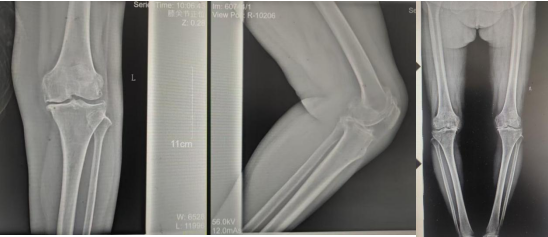

術(shù)前影像資料

因張女士患有高血壓病2級(高危)、心律失常(竇緩)且伴有肺部感染等并發(fā)癥。穆志亮主任和葉龍安主治醫師根據張女士的病情制定詳細手術(shù)方案,建議在全麻下行“左人工全膝關(guān)節置換術(shù)”。

術(shù)后影像資料